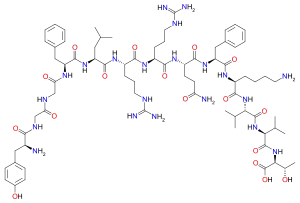

Opioid peptides

Dynorphins

Structures

| Dynorphins | ||||

|---|---|---|---|---|

Big dynorphin Big dynorphin |

Dynorphin A Dynorphin A |

Dynorphin B Dynorphin B | ||

Endomorphins

Endorphins

Structures

Enkephalins

Structures

| Enkephalins | ||||

|---|---|---|---|---|

DAMGO DAMGO |

||||

Propeptides

Others / unknown

- Adrenorphin

- Amidorphin

- Biphalin

- Casokefamide

- Casomorphins

- Cytochrophin-4

- DALDA (Tyr-D-Arg-Phe-Lys-NH2)

- Deltorphin I

- Deltorphin II

- Deprolorphin

- Dermorphin

- DPDPE

- Frakefamide

- Gliadorphin

- Gluten exorphins

- Hemorphin-4

- Metkefamide

- Morphiceptin

- Nociceptin

- Octreotide

- Opiorphin

- Rubiscolin

- Soymorphins

- Spinorphin

- TRIMU 5

- Tynorphin

- Valorphin

- Zyklophin

Structures

| Other or unknown opioid peptides | ||||

|---|---|---|---|---|

Adrenorphin Adrenorphin |

Amidorphin Amidorphin |

Casomorphin Casomorphin |

DALDA DALDA |

|

DPDPE DPDPE |

Endomorphin-1 Endomorphin-1 Endomorphin-2 Endomorphin-2 |

Gliadorphin Gliadorphin |

Morphiceptin Morphiceptin | |

Nociceptin Nociceptin |

Octreotide Octreotide |

Opiorphin Opiorphin |

Rubiscolin Rubiscolin |

TRIMU 5 TRIMU 5 |